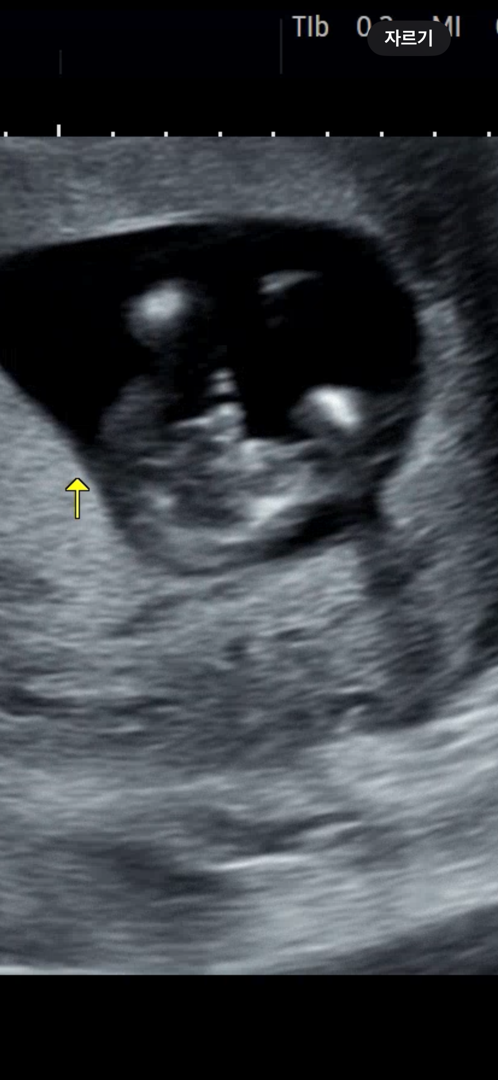

혹시 아들 같나요 딸 같나요?? 다리 사이입니다

다리사이에 혹시 딸 같나요 아들 같나요?? 댓글에 사진 하나 더 첨부할게요 같은 날 찍은 사진입니다

이사진도 있어요!!